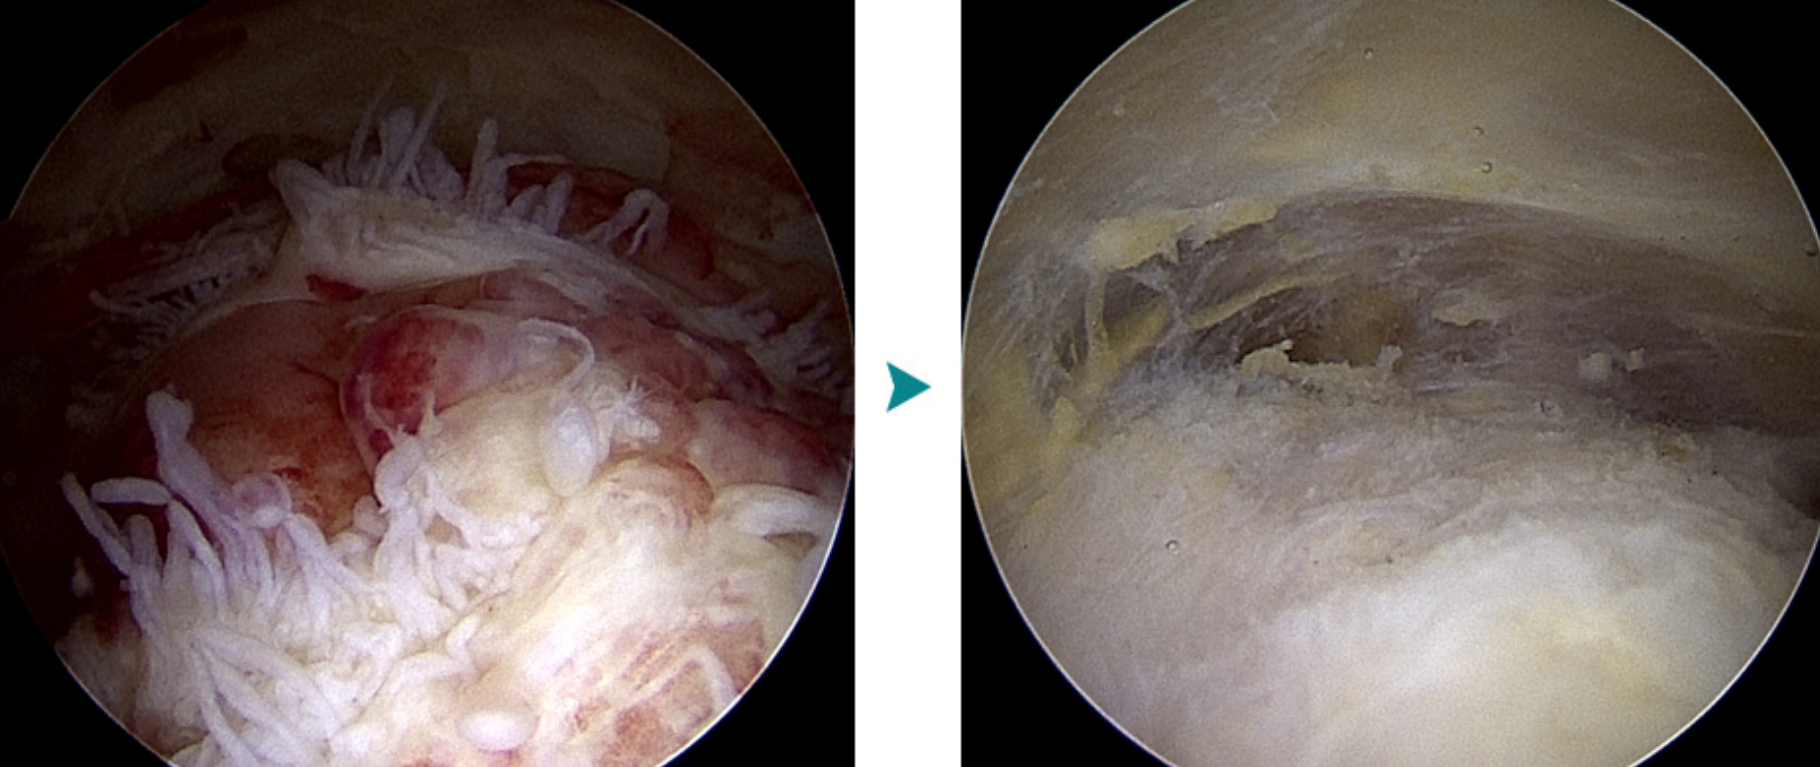

♦ 관절경 혹은 절개에 의한 점액낭 제거술

다음과 같은 경우에는 수술적 치료가 필요합니다.

☛2차 감염(고름, 열 동반)

☛ 재발이 심한 만성 점액낭염

☛보존적 치료 및 주사치료에 반응하지 않는 경우

☛최근에는 기존의 절개 방식보다 회복 속도가 빠른 관절경 수술이 일반적으로 선호됩니다.